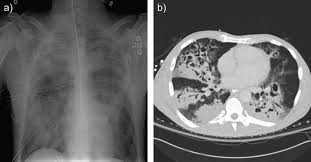

Mrsa Overview And More from www.verywellhealth.com The bacteria can cause an infection on the skin and in the lungs. This type of bacteria is resistant to many different antibiotics. About two in every 100 people carry mrsa; Although many people carry mrsa bacteria in their nose, most do not develop serious mrsa infections. Aureus causes a number of important infections both in the community and in the healthcare setting. A vaccination was the cause of this infection. Mrsa strains can be identified by seeing which antibiotics kill the germs found on testing. Best treatments may involve antibiotics, rest and pain relievers.

Staph and mrsa often cause itchy, painful skin infections, but internal infections are common too. Learn mrsa infection causes (methicillin resistant staphylococcus aureus superbug), symptoms, treatment, and transmission by mrsa carriers. Staph infection symptoms range from mild to severe. Methicillin resistant staph aureus (mrsa) causes a bacterial infection that is resistent to antiobiotics. A carrier means that a person has no symptoms, but the mrsa bacteria are living in their nose or on their skin. Where are mrsa and staph found? However, there is marked geographical variation in mrsa burden owing to several factors. Mrsa lives harmlessly on the skin of around 1 in 30 people, usually in the nose having mrsa on your skin does not cause any symptoms and does not make you ill. Aureus can sometimes get into the bloodstream and travel to internal parts of the body to cause more serious infections. Anywhere on your skin and commonly, in your nose and other moist locations. Strains of these bacteria (commonly termed staph) may cause infection in almost any part or organ system in humans. Most mrsa infections occur in people who've been in hospitals or other health care settings. Educational video describing the condition of mrsa (methicillin resistant saphylococcus aureus) mrsa is a contagious bacteria that mya cause infection.

Mrsa strains are further characterized as superbugs because mrsa. This resistance makes it challenging to treat. In some cases, it causes pneumonia (lung. Because antibiotics are widely used in hospitals, hospital bloodstream infection is a common cause of death in people with severe burns. Staph and mrsa often cause itchy, painful skin infections, but internal infections are common too. Although common, inflamed sinuses (sinusitis) that become infected cause pain, fever, fatigue and cough. However, there is marked geographical variation in mrsa burden owing to several factors. Mrsa is difficult to treat because it is mrsa was first recognized in 1961. Aureus can sometimes get into the bloodstream and travel to internal parts of the body to cause more serious infections. Symptoms are a deep red color and swelling. Best treatments may involve antibiotics, rest and pain relievers. It is resistant to several common antibiotics. Mrsa lives harmlessly on the skin of around 1 in 30 people, usually in the nose having mrsa on your skin does not cause any symptoms and does not make you ill.

Mrsa Infection Symptoms Treatment Pictures Contagious Period from images.medicinenet.com A common place for mrsa colonization with mrsa is inside the nose. It is resistant to several common antibiotics. People sometimes call it a superbug because it is resistant to numerous antibiotics. Anywhere on your skin and commonly, in your nose and other moist locations. However, there is marked geographical variation in mrsa burden owing to several factors. Osteomyelitis is generally caused by staphylococcus, which reaches the bones via the blood stream from a distant focus, often a throat infection. About two in every 100 people carry mrsa; Because antibiotics are widely used in hospitals, hospital bloodstream infection is a common cause of death in people with severe burns.

Staphylococcus aureus (s aureus) colonises the nasal cavity and skin of carriers and can cause infection in open or unhealed surgical wounds. Where are mrsa and staph found? Mrsa is difficult to treat because it is mrsa was first recognized in 1961. Best treatments may involve antibiotics, rest and pain relievers. Sinusitis is an inflammation of the sinuses that can cause them to get blocked and filled with fluid. A common place for mrsa colonization with mrsa is inside the nose. These bacteria naturally live in the nose and on the skin and generally don't cause any harm. Mrsa strains are further characterized as superbugs because mrsa. This type of bacteria is resistant to many different antibiotics. It is resistant to several common antibiotics. Although common, inflamed sinuses (sinusitis) that become infected cause pain, fever, fatigue and cough. This resistance makes it challenging to treat. A vaccination was the cause of this infection.